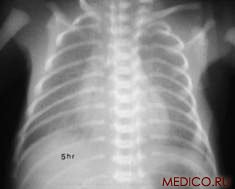

А) Б)

Рис 1. Рентгенограммы легких: а) взрослого мужчины; б) ребенка.

При рентгенологическом исследовании грудной клетки ясно видны два светлых «легочных поля», по которым судят о легких, так как вследствие наличия в них воздуха они легко пропускают рентгеновские лучи и дают просветления. Оба легочных поля отделены друг от друга интенсивной срединной тенью, образуемой грудиной, позвоночником, сердцем и крупными сосудами. Эта тень составляет медиальную границу легочных полей; верхняя и латеральная границы образованы ребрами. Снизу находится диафрагма.

Верхняя часть легочного поля пересекается с ключицей, которая отделяет надключичную область от подключичной. Ниже ключицы на легочное поле наслаиваются пересекающиеся между собой передние и задние части ребер. Они располагаются косо: передние отрезки – сверху вниз и медиально; задние – сверху вниз и латерально. Хрящевые части передних отрезков ребер при рентгеновском исследовании не видны. Для определения различных пунктов легочного поля пользуются промежутками между передними отрезками ребер (межреберья).

Собственно легочная ткань видна в светлых ромбовидных межреберьях. В этих местах виден сетевидный или пятнистый рисунок, состоящий из более или менее узких тяжеобразных теней, наиболее интенсивных в области корней легких и постепенно убывающих в своей интенсивности от срединной тени сердца к периферии легочных полей. Это так называемый легочный рисунок. По обе стороны тени сердца на протяжении передних отрезков II – V ребер располагаются интенсивные тени корней легких. От тени сердца они отделены небольшой тенью главных бронхов. Тень левого корня несколько короче и уже, так как она больше прикрывается тенью сердца, чем справа.

Анатомической основой тени корней и легочного рисунка является сосудистая система малого круга кровообращения – легочные вены и артерии с радиарно отходящими от них ветвями, рассыпающимися в свою очередь на мелкие веточки. Лимфатические узлы в норме не дают тени.

Анатомический субстрат легочного рисунка и теней корней особенно ясно заметен при томографии (послойной рентгенографии), которая дает возможность получить снимки отдельных слоев легкого без наслоения на легочное поле ребер. Легочной рисунок и корневые тени есть симптом нормальной рентгеновской картины легких в любом возрасте, включая и ранний детский. При вдохе видны просветления, соответствующие плевральным синусам.

Рентгенологический метод исследования позволяет видеть изменения в соотношениях органов грудной клетки, происходящие при дыхании. При вдохе диафрагма опускается, куполы ее уплощаются, центр передвигается несколько книзу. Ребра поднимаются, межреберные промежутки делаются шире, Легочные поля становятся светлее, легочный рисунок отчетливее. Плевральные синусы «просветляются», становятся заметными. Сердце приближается к вертикальному положению. При выдохе возникают обратные соотношения.